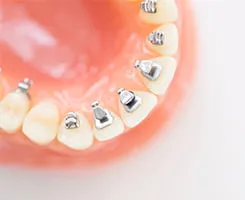

裏側(舌側)矯正

歯の裏側にブラケットという金属の装置とワイヤーをつける目立ちにくい矯正治療です。